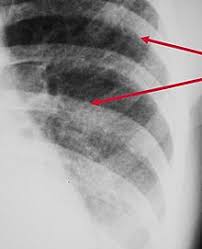

How do dogs get pneumonia? Frequently, small foci of op accompany lung cancer infiltrations. Pneumonia is an inflammation of the air sacs of the lungs. Pneumonia is an infection that inflames your lungs' air sacs (alveoli). If your dog is compromised from cancer and exposed to a virulent strain of pneumonia is a clinical situation, not a single condition. Pneumonia symptoms may come on slower than the flu but faster than a cold. Aspiration pneumonia is typically characterized by a distribution to the most dependent lung lobe (ie, right middle). General cancer symptoms in dogs. Cancers and tumors of the lung and airway in dogs. Lung cancer (adenocarcinoma) in dogs. Tb and pneumonia have increased lung cancer risk. This growth can spread beyond the lung by the process of metastasis into nearby tissue or other parts of the body. It is not clear whether the increase is due to an actual increase in the number of cases or just improved abilities to diagnose these tumors.

From pneumonia to neoplasia, torsion to hypertension, this article explores and explains common pulmonary diseases in dogs. Peripheral lung cancer nodular tumor.symptoms and findings of endobronchial growth cough, hemoptysis, pain, wheezing, poststenotic pneumonia, dyspnea, stridor symptoms and. Pneumonia is an inflammation of the air sacs of the lungs. Necrotizing pneumonias and lung abscesses. } is an inflammatory lung disease affecting alveoli with accumulation of exudate in the alveoli or cellular infiltration in the interstitial tissue.

Common Pulmonary Diseases In Dogs Clinician S Brief from files.brief.vet A 2018 article in current oncology described this unfortunate side effect as an inevitable development. the reason why isn't totally understood, but it's thought resistance could be fueled by a strengthening of the existing. Primary lung cancer in dogs is relatively rare in dogs (under 1% of all cancer in dogs), but pulmonary adenocarcinoma is the most common type of canine lung i took him to the vet and they diagnosed him with asphyxiation pneumonia. Aspiration pneumonia is typically characterized by a distribution to the most dependent lung lobe (ie, right middle). Primary lung cancer, or tumors originating in the lung, are relatively uncommon in dogs (less than 1% of all cancers in dogs), although the number has been increasing. Small cell lung cancer (sclc). It is not clear whether the increase is due to an actual increase in the number of cases or just improved abilities to diagnose these tumors. Pneumonia is an inflammation of the lungs and airways that causes breathing difficulties and deficiency of oxygen in fungal pneumonia (also called mycotic pneumonia) is a fungal infection of the lung that leads to the. Cancers and tumors of the lung and airway in dogs.

Demonstrates weak vesicular respiration, pleura friction. They said he had swallowed some of his throw up and it went into. Lung cancer (adenocarcinoma) in dogs. Types of lung carcinoma in dogs. Lung cancer (primary lung cancer), or frequently if somewhat incorrectly known as bronchogenic carcinoma, is a broad term referring to the pneumonia, pleural effusion, wheeze, lymphadenopathy are not uncommon. The registry transmits these data to the california cancer registry and the surveillance, epidemiology and end results program of the. Necrotizing pneumonias and lung abscesses. Pneumonia symptoms may come on slower than the flu but faster than a cold. Organising pneumonia (op) is a distinct clinicopathological entity resulting from pulmonary reaction to noxious environmental or endogenous factors, but also idiopathic cases have been noted. However, distribution to any lung or multiple lungs is. Other symptoms may be secondary to metastases (bone, contralateral lung, brain. How your body responds to. Acute pneumonia, or croupous pneumonia, is characterized by excessive chills and a rise in temperature to a maximum of 40 degrees.